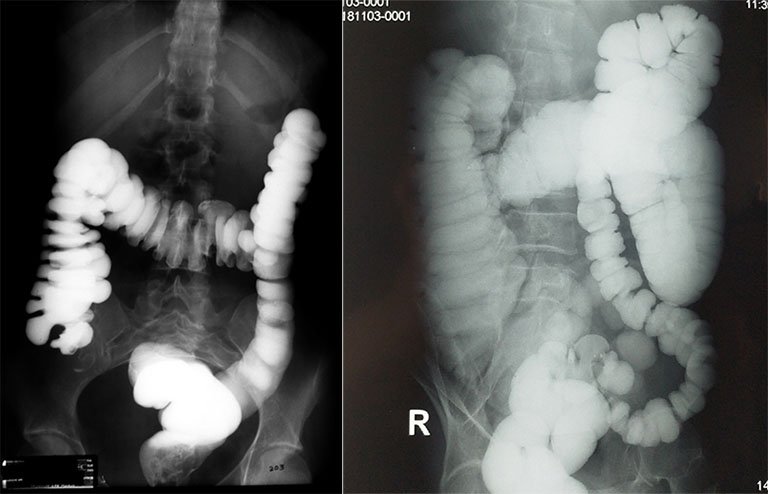

Chụp X-quang đại tràng cản quang là một Xét nghiệm dùng X-quang để có thể phát hiện những thay đổi hoặc bất thường ở ruột già (đại tràng) khi được bơm thuốc cản quang. Đây là một trong những phương pháp Chẩn đoán hình ảnh hỗ trợ đắc lực cho việc chẩn đoán và điều trị bệnh đại tràng: như viêm, ung thư, polyp đại tràng.

Thuốc cản quang là một loại chất lỏng được bơm vào lòng trực tràng của bạn sau khi toàn bộ khung đại tràng đã được chuẩn bị kỹ lưỡng. Loại thuốc này có chứa một chất kim loại (barium) bao phủ lớp niêm mạc nằm trong cùng của lòng đại tràng. Thông thường, tia X phản ánh hình ảnh của các mô mềm rất kém nhưng khi có lớp phủ barium, khung đại tràng sẽ hiện lên rất rõ ràng.

Trong trường hợp barium là chống chỉ định, không khí có thể được bơm vào đại tràng, mở rộng lòng ruột và cải thiện chất lượng hình ảnh, những tổn thương được dựng hình chính xác hơn. Bản chất không khí không phải là chất cản quang nhưng kỹ thuật này vẫn được gọi là chụp X-quang đại tràng tương phản không khí.